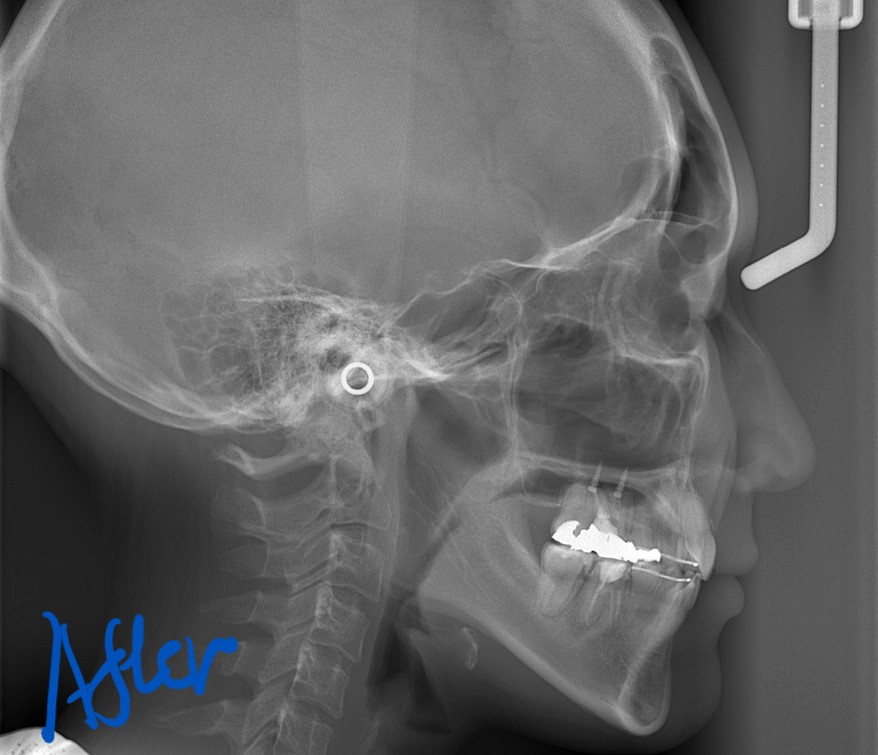

矯正後の状態をレントゲン写真で確認すると、

では、矯正治療前後の「レントゲン写真」や「笑顔、口元の写真」などを比較してみましょう。

まずはレントゲン写真の比較です。

左側が矯正治療前、右側が矯正治療後